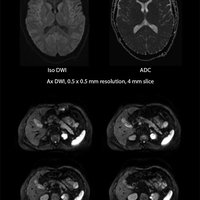

• MultiBand SPEEDER beschleunigt Aufnahmedauer hochaufgelöster Diffusionsbilder

• Fast 3D reduziert Aufnahmezeit von mVox-Scans um bis zu 50%